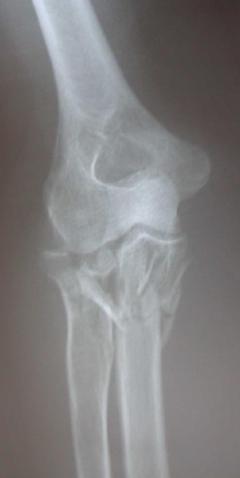

Περίπτωση 1ου ασθενούς

Προεγχειρητική